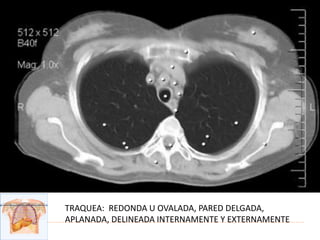

TRAQUEA: REDONDA U OVALADA, PARED DELGADA,

APLANADA, DELINEADA INTERNAMENTE Y EXTERNAMENTE